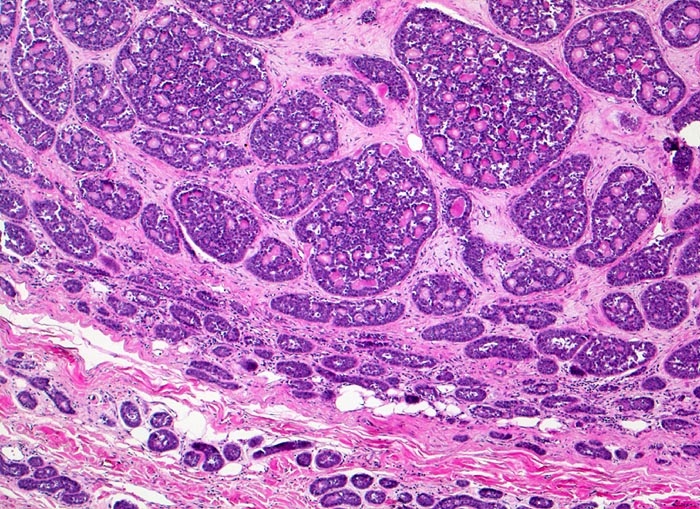

Adenoidzystische Karzinome zeigen drei Wachstumsmuster (in abnehmender Reihenfolge): kribriform, tubulär und solide. Die Hohlräume in den kribriformen Arealen entsprechen keinen echten Drüsenlumina, sondern sind Bestandteil des Tumorstromas. Sie enthalten PAS positives Sekret oder hyaline Substanzen. Die strangförmigen Tubuli begleitet von hyalinem Stroma. Typischerweise (allerdings nicht im vorliegenden Präparat) kann eine Perineuralscheideninvasion nachgewiesen werden. Kleine Tumoren können scharf begrenzt sein, grössere Tumoren wachsen infiltrativ.

• Reste einer rein serösen Speicheldrüse (rechts).

• Unscharf begrenzter, aus kribriformen, tubulären und soliden Zellformationen aufgebauter infiltrativ wachsender Tumor.

• Mikrozystische Hohlräume in den kribriformen Tumorarealen enthalten eosinophiles hyalines Material.

• Tubuli mit zentralem Lumen werden ausgekleidet von einer inneren helleren Epithelschicht und einer äusseren dunkleren Myoepithelschicht.

• Basaloide kleine Tumorzellen mit wenig Zytoplasma.